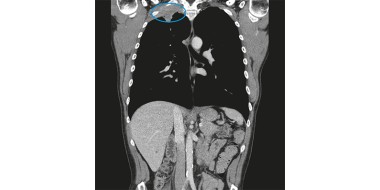

• De pancoasttumor: witte raaf bij schouderpijn

Een 50-jarige man bezoekt het spreekuur met pijn rondom zijn rechterschouder. De pijn is er sinds een week en zit ter hoogte van zijn rechterbovenarm, oksel, schouderblad en aan de bovenzijde van zijn schouder. De patiënt voelt ook een licht drukkend gevoel op de rechter…